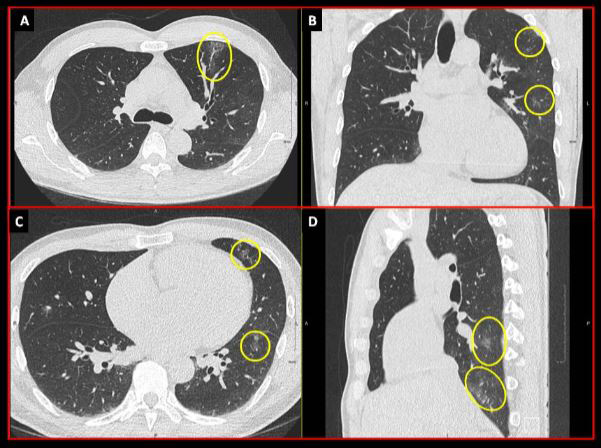

A computerized tomography scan (CT scan for short) uses three-dimensional X-ray technology to create cross-sectional pictures of a patient’s bones, blood vessels and soft tissues. A cardiologist may recommend a scan to detect or monitor a disease or condition of the heart, inform an upcoming procedure or surgery, detect internal injuries, or evaluate the effectiveness of various treatments.

“When a patient with symptoms of COVID-19 is admitted to hospital, it is likely they will receive a CT scan and a nasopharyngeal swab,” says Dr. Andrew Crean, co-director of the cardiac MRI service at the UOHI. But according to Crean, the real question is, What do you do with patients who show up without symptoms of virus or whose symptoms are very minor?

“We’re increasingly finding quite a proportion of people who test positive for COVID-19 are asymptomatic,” says Crean. “We need to know who these people are – the concern being people who feel well may be presenting to the hospital as unknowing carriers and transmitters of disease.”

Dr. Crean and his colleagues at the UOHI are currently studying the potential for CT scan technology as a first step in detecting positive cases of COVID-19.